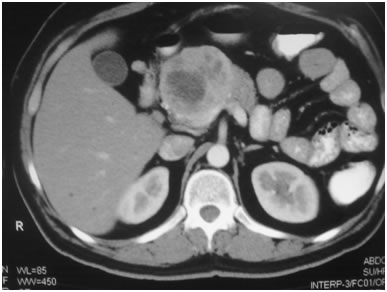

CT Scan of Infected Pancreatic necrosis

ANP is a clinical condition affecting not only the pancreas but other organ systems as well. It can be a dreaded and severely life threatening condition if timely therapy is not instituted. The inherent mortality of this condition again has fallen from 40% to 15% in our centre. Initial therapy of recussitation& conservative management of SIRS needs to be done in an ICU to tide over the first couple of weeks. Intervention (Radiological or Surgical) is requiredto tackle infected Acute Necrotic Collection (ANC) or Walled Of Necrosis (WON).Surgical intervention is generally delayed to atleast 4 weeks if possible so that the necrotic elements separate from the viable pancreas. At times a second or third debridement may also be required albeit rarely.